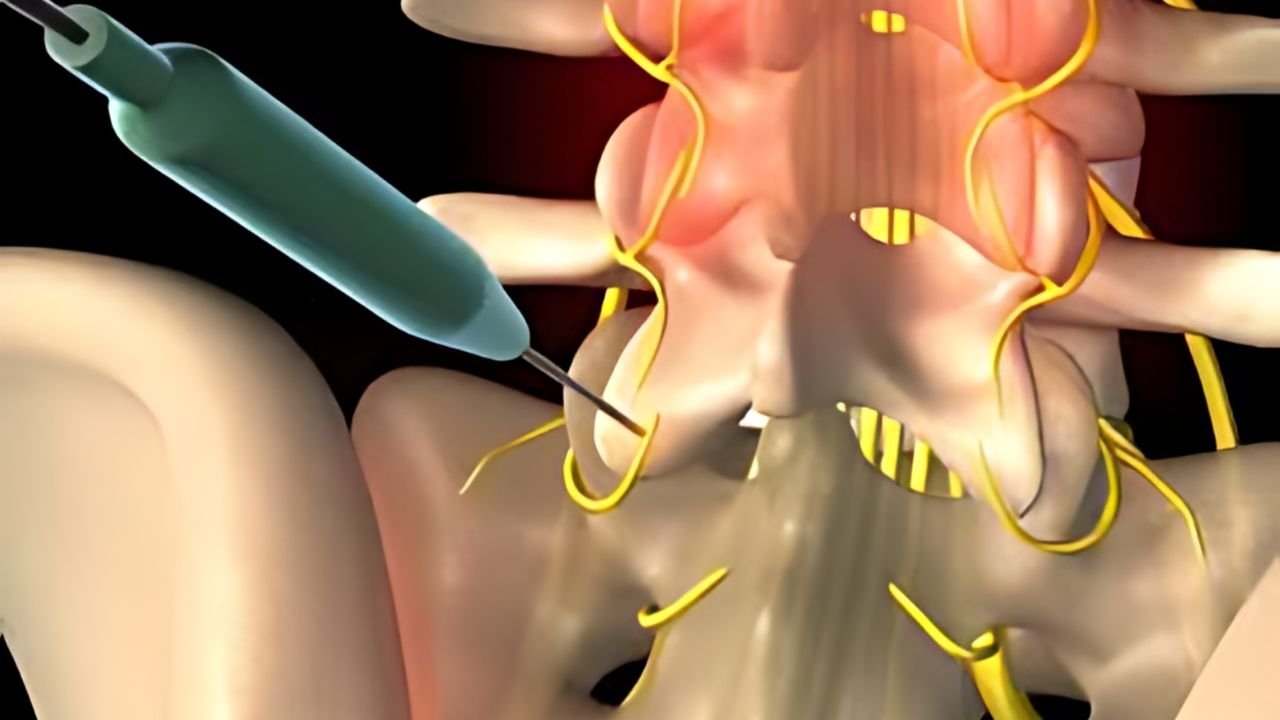

A consulta é o momento mais importante. Realizamos uma escuta ativa da sua história, seguida de um exame físico detalhado e análise minuciosa de exames de imagem. O objetivo não é apenas tratar o sintoma, mas identificar a origem exata da dor para traçar o melhor plano terapêutico.

É uma área da medicina dedicada ao diagnóstico preciso e tratamento

de dores agudas e crônicas. Utilizamos técnicas avançadas para bloquear ou modular os sinais dolorosos, visando restaurar a funcionalidade e reduzir o sofrimento .

São técnicas onde utilizamos ultrassom ou radioscopia em

tempo real para guiar agulhas e instrumentos com precisão milimétrica até o alvo da dor. Isso garante maior segurança e eficácia.